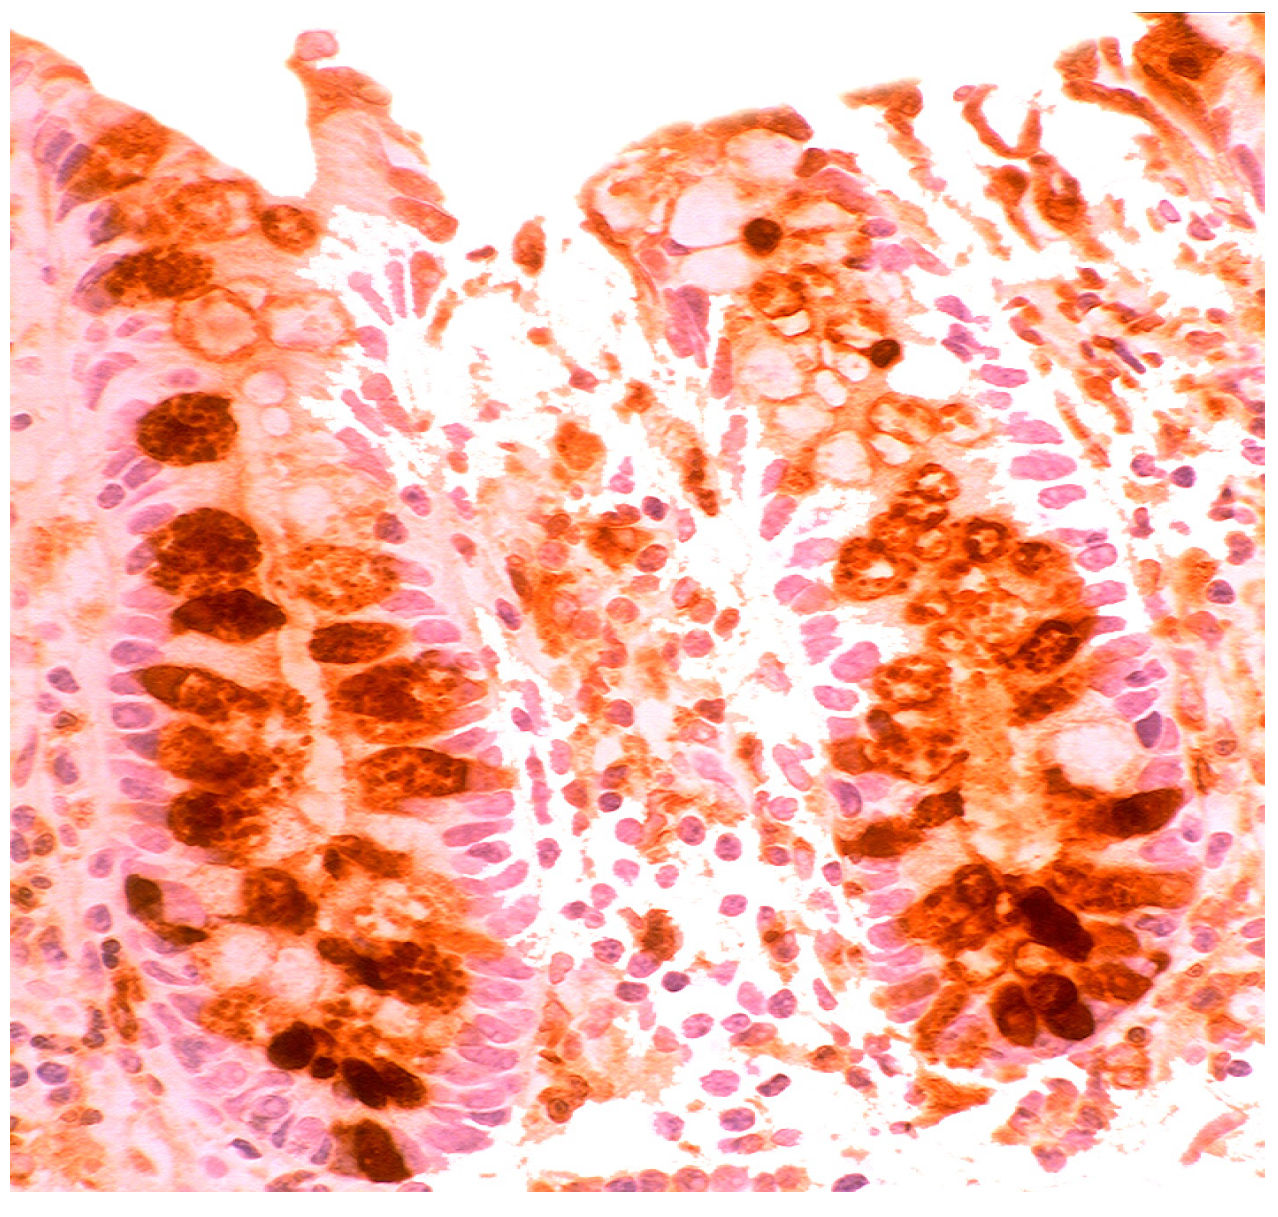

In the normal duodenal mucosa, Paneth cells produce lysozyme. In coeliac disease, lysozyme is up-regulated in goblet cells, in dilated crypts with mucus-metaplasia (Figure 9), a phenomenon more apparent in the bulbus [10] (Figure 10). It is not inconceivable that the lysozyme-rich mucus metaplasia mirror stem cell adaptation to the signals generated by the pathogenic bacteria present in the duodenal microenvironment [63].

Chronic atrophic duodenitis (celiac disease). Villous atrophy showing lysozyme-rich mucus metaplasia in the lower part of the crypts. Note lysozyme expressing goblet cells (lysozyme immunostain, ×10).

Chronic atrophic duodenitis (celiac disease). Villous atrophy showing extensive lysozyme-rich mucus metaplasia of the crypts. Note absence of Paneth cells (lysozyme immunostain, ×10).